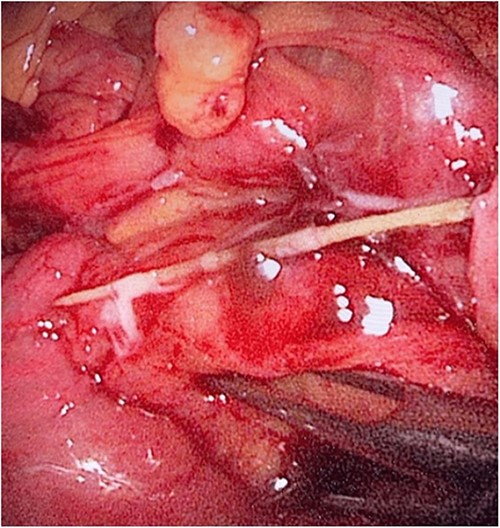

During her hospital stay, the patient showed no improvement regarding abdominal pain, nausea, or abdominal exam. Therefore, she was offered a laparoscopic exploration to verify the diagnosis of a FB to which she agreed. She was taken to the operating room, and the exploration showed an inflammatory process in the LLQ (Fig. 3) with the sigmoid colon attached to the area of the inflammatory reaction. A FB was found in the mesentery of two loops of the ileum 100 cm from the ileocecal junction (Figs 4 and 5). Removal of the FB safely and milking of the small bowel showed no leakage of bowel contents (Fig. 6). And, exploring the rest of the abdomen showed no other pathology and normal ovaries (Figs 7 and 8); the procedure was uneventful. The FB was identified as a toothpick, 3 cm in length (Fig. 9).